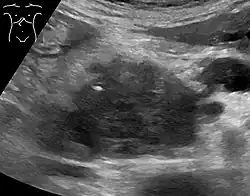

Abdominal ultrasonography of pancreatic cancer (presumably adenocarcinoma), with a dilated pancreatic duct to the right.

Medical imaging techniques, such as computed tomography (CT scan) and endoscopic ultrasound (EUS) are used both to confirm the diagnosis and to help decide whether the tumor can be surgically removed (its "resectability").[12] On contrast CT scan, pancreatic cancer typically shows a gradually increasing radiocontrast uptake, rather than a fast washout as seen in a normal pancreas or a delayed washout as seen in chronic pancreatitis.[58] Magnetic resonance imaging and positron emission tomography may also be used,[2] and magnetic resonance cholangiopancreatography may be useful in some cases.[34] Abdominal ultrasound is less sensitive and will miss small tumors, but can identify cancers that have spread to the liver and build-up of fluid in the peritoneal cavity (ascites).[12] It may be used for a quick and cheap first examination before other techniques.[59]